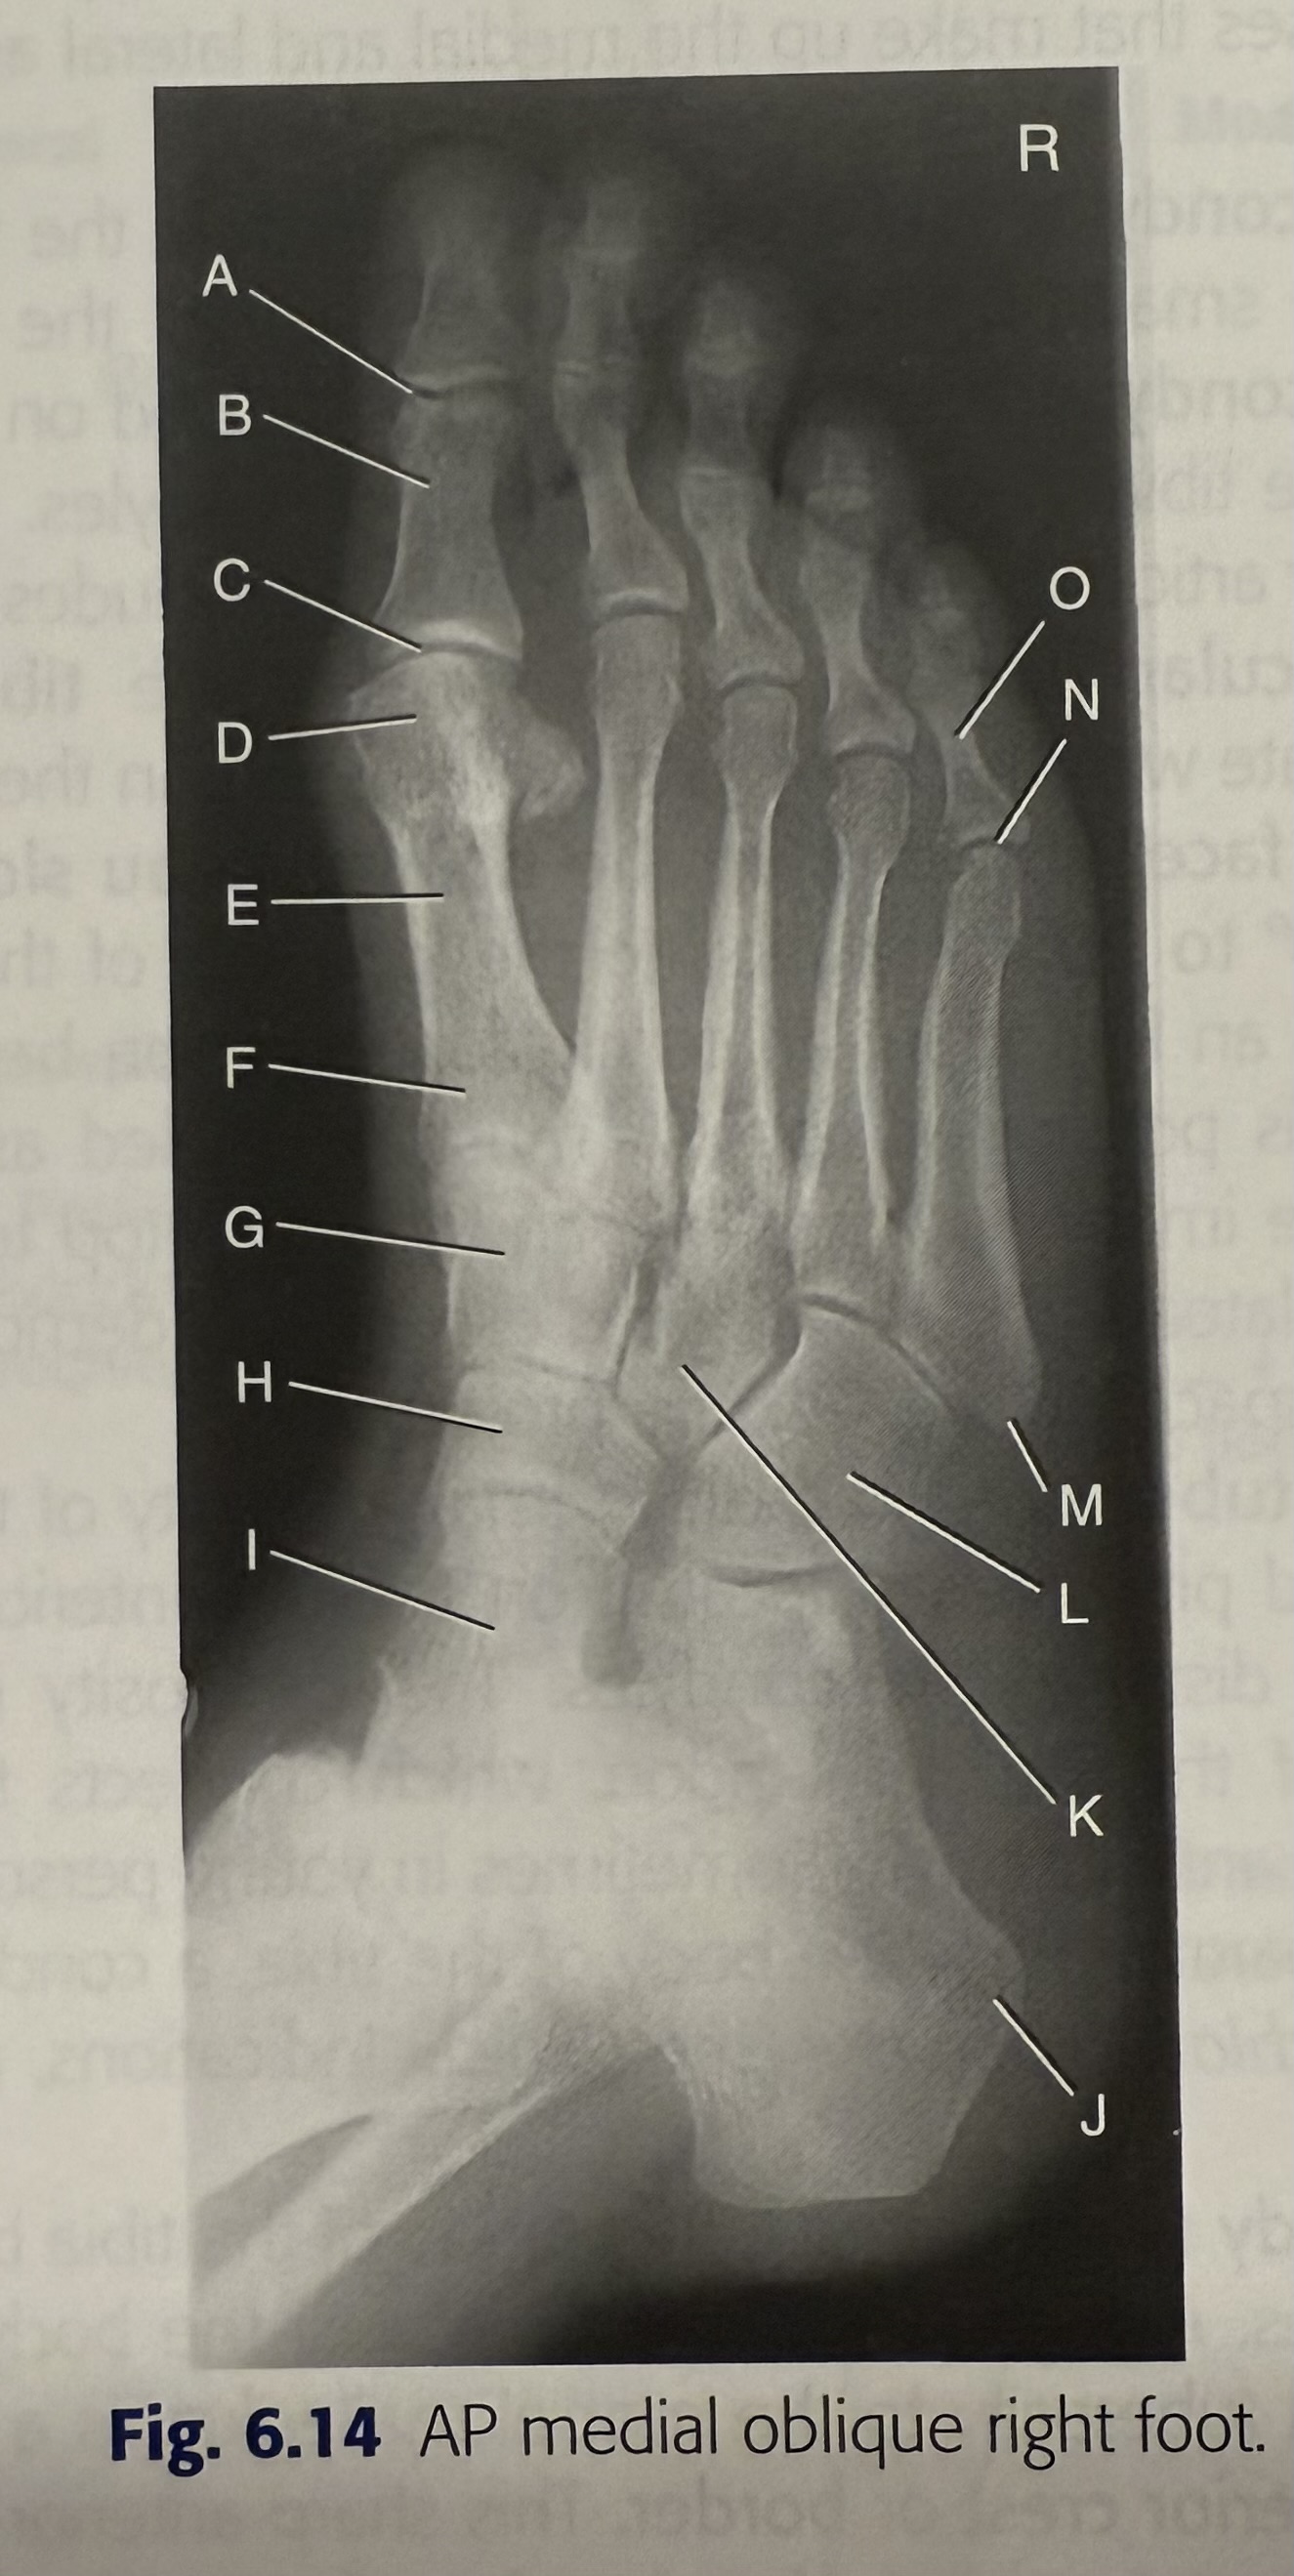

<p>A</p>

A

IP joint of 1st digit of right foot

95

New cards

<p>B</p>

B

proximal phalanx of 1st digit of right foot

96

<p>C</p>

C

MTP joint of 1st digit of right foot

97

<p>D</p>

D

head of 1st metatarsal

98

<p>E</p>

E

body of 1st metatarsal

99

<p>F</p>

F

base of 1st metatarsal

100

<p>G</p>

G

intermediate cuneiform